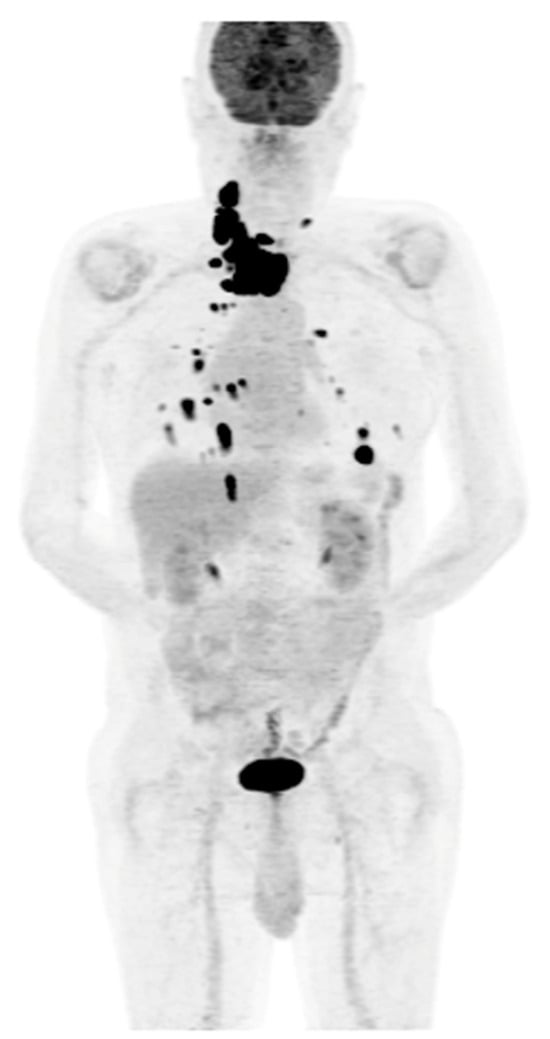

Figure 5.

Maximum-intensity projection (MIP) PET/CT with [18F]FDG. Multiple foci of increased [18F]FDG accumulation are visible in the neck (unresectable local recurrence), with the presence of metastatic lesions in the lymph nodes and in both lungs. Patient qualified for TKI (sorafenib) therapy with stable disease since 2022.